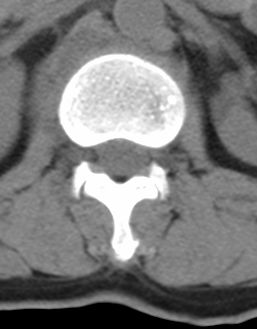

标题: CT22439:腰椎低密度病灶(腰椎血管瘤) [打印本页]

标题: CT22439:腰椎低密度病灶(腰椎血管瘤)

患者 女 54岁 外伤后检查发现l1椎体局部密度减低,请问这是什么病灶?

考虑腰椎血管瘤

椎体内部局限性骨小梁稀疏、粗大改变,周围未见软组织肿块,首先考虑椎体血管瘤。

l1椎体血管瘤可能性大;建议必要时行mri检查。